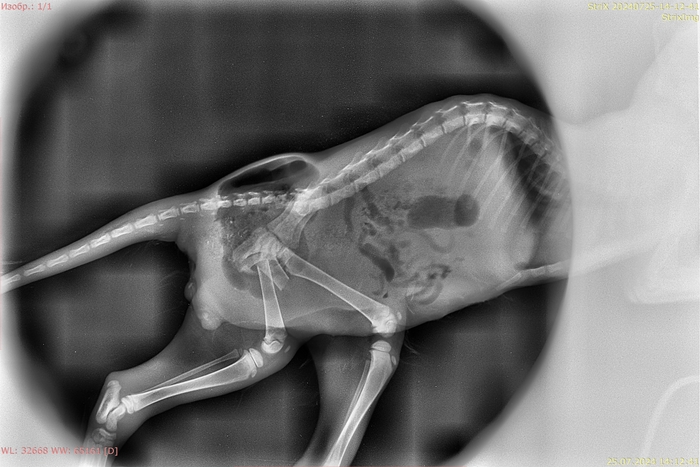

Котенка забрали в клинику, врач нам сказал, что они позвонят, когда закончится операция. Еще на приеме на узи узнали, что у него перитонит, но мочевой пузырь цел. Ждали звонка после операции, чтобы все сообщить.

Операцию экстренно провели в клинике Зоовет, времени не было, обзванивали по спискам из чата, которые вы нам советовали. Кто-то отказывался брать такого маленького, кто-то в отпуске, у кого-то не было мест либо хирургов. Выбирали ближайшие подходящие клиники, потому что открылась грыжа с содержимым кишечника, согласились взять только две, но Зоовет была сильно ближе (в 15 минутах) и со свободной бригадой хирургов.

Первая операция прошла успешно, ушили толстый кишечник, почистили брюшную полость, но глубоко не лезли в таз и в кости. Печень, селезенка, мочевой, и другие органы целы.

Но есть и новость. Оказалось, что у него под шерстью было много абсцессов, то есть дырочек, которые стали заметны после бритья перед операцей. Теперь мы наконец знаем что послужило причиной травмы малыша, это укус собаки. Помимо абсцессов произошел множественный некроз мышц бедра и отрыв лоскутов кожи, которые тоже отмирали. По возможности часть сейчас устранили, но полностью пока не смогли. Операция длилась почти 3 часа.